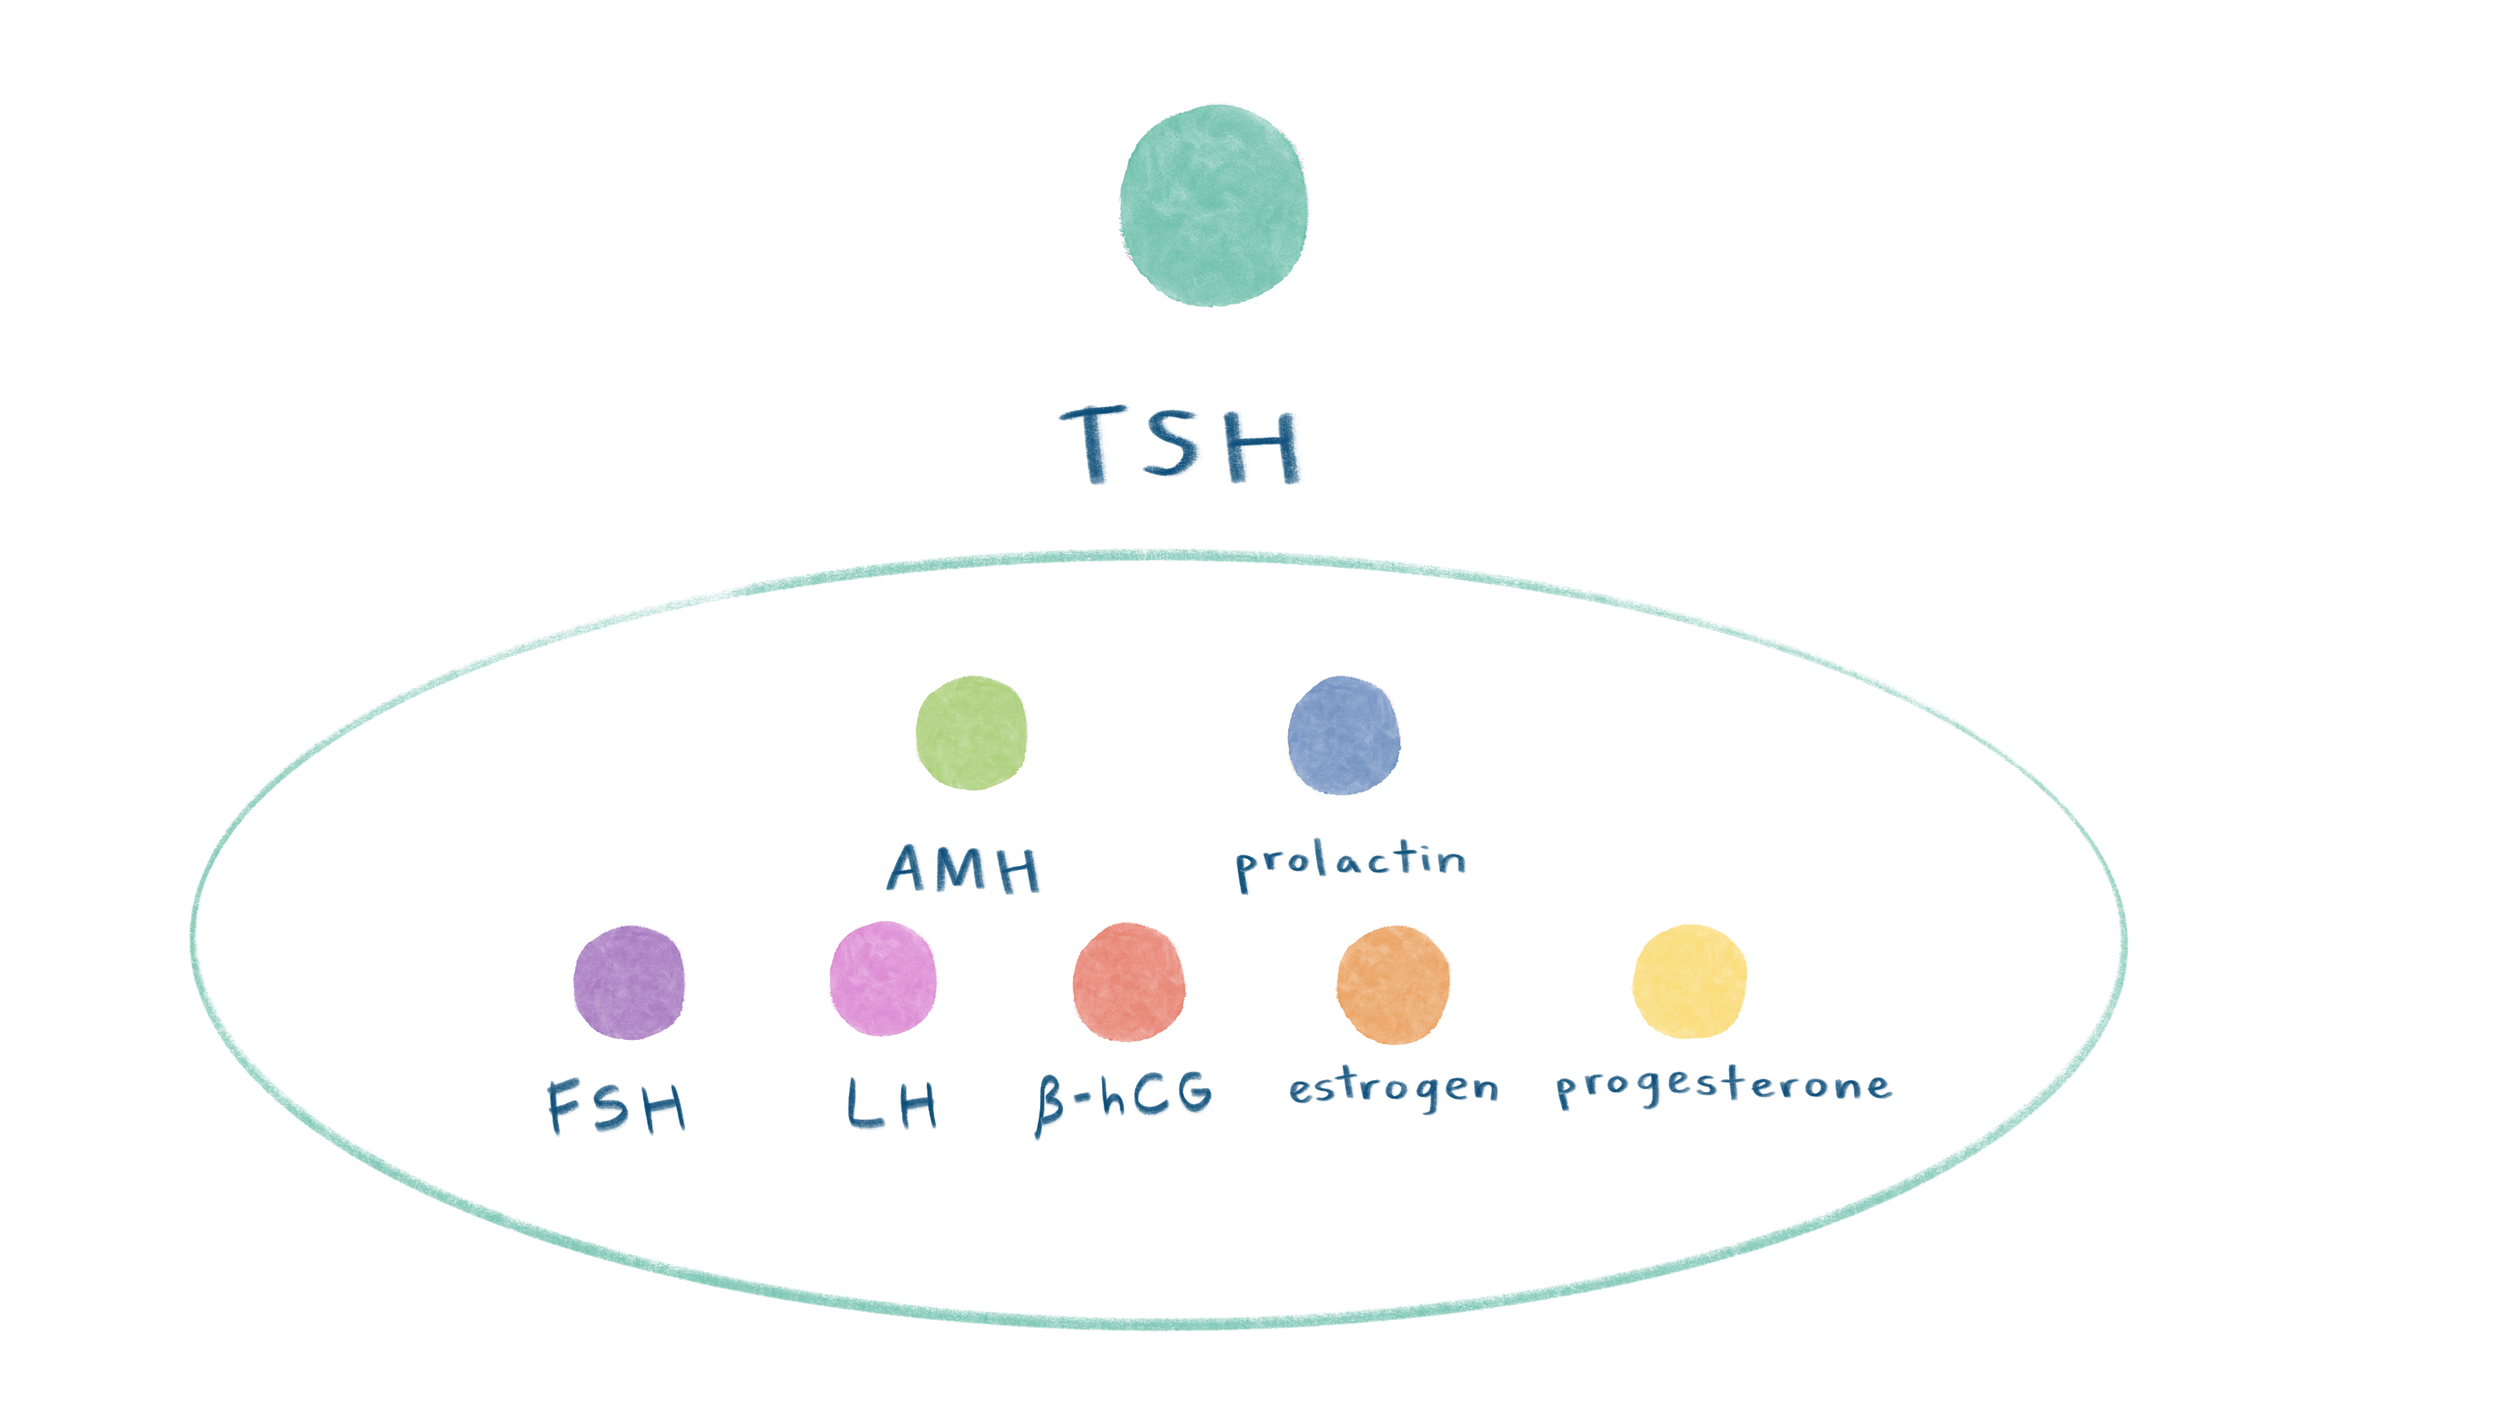

Pregnancy hormones

Pregnancy hormones